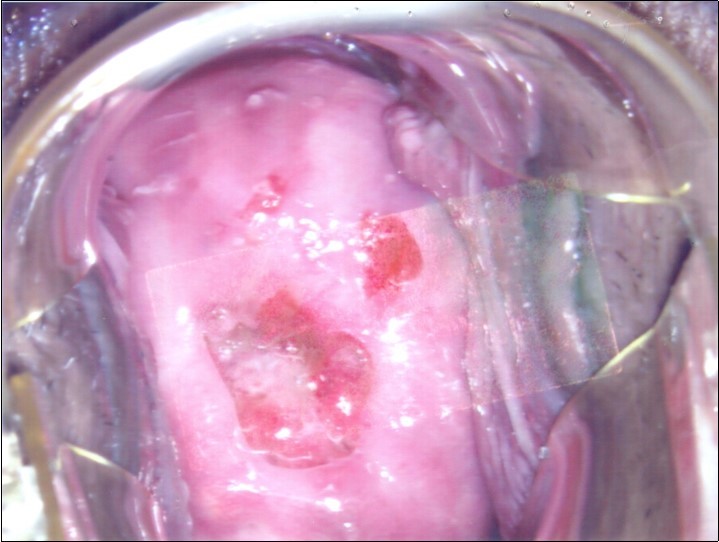

At initial presentation, colposcopy was unsatisfactory due to inadequate visualisation of the transformation zone. (Figure 1) Severe cervico-vaginitis was seen, with frothy white discharge and contact bleeding. A small focus of aceto-white epithelium was seen at the 1 o’clock region surrounded by peeling, friable epithelium. HPV DNA test, as well as cervical punch biopsy of the focus of aceto-white epithelium were taken.

Figure 2a.Repeat colposcopy (low magnification)